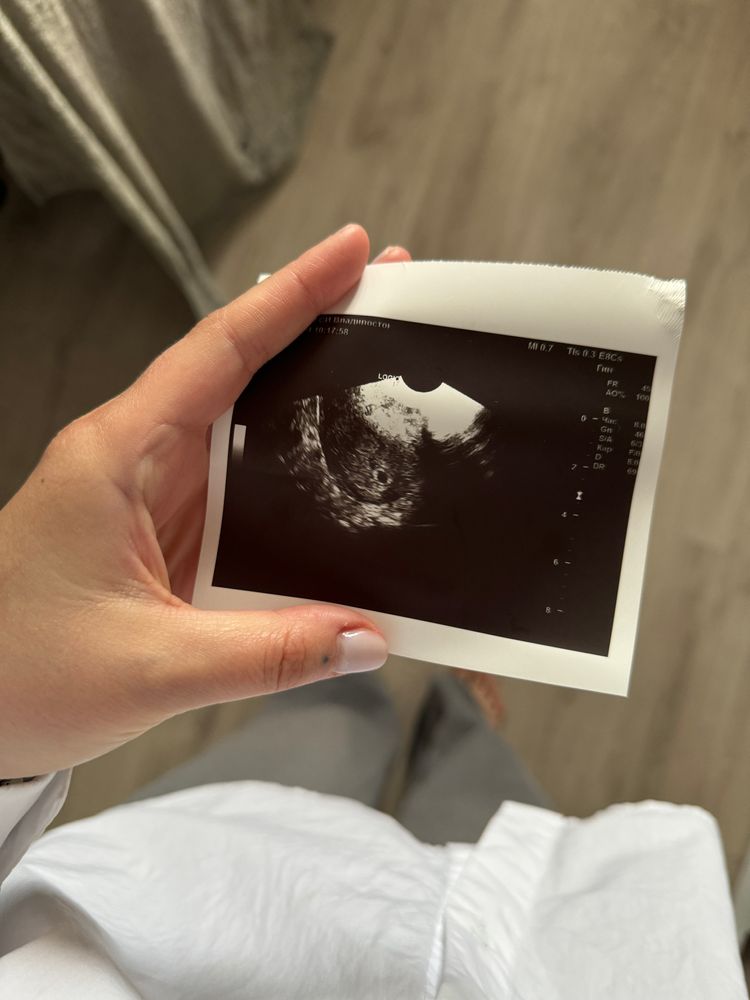

(Фото от 19.06)

15.06 ХГЧ - 1980 , увидели плодное яйцо 6мм + развивающийся ЖМ

Приложила фото с 15.06 ( кажется даже ЖМ не видно)